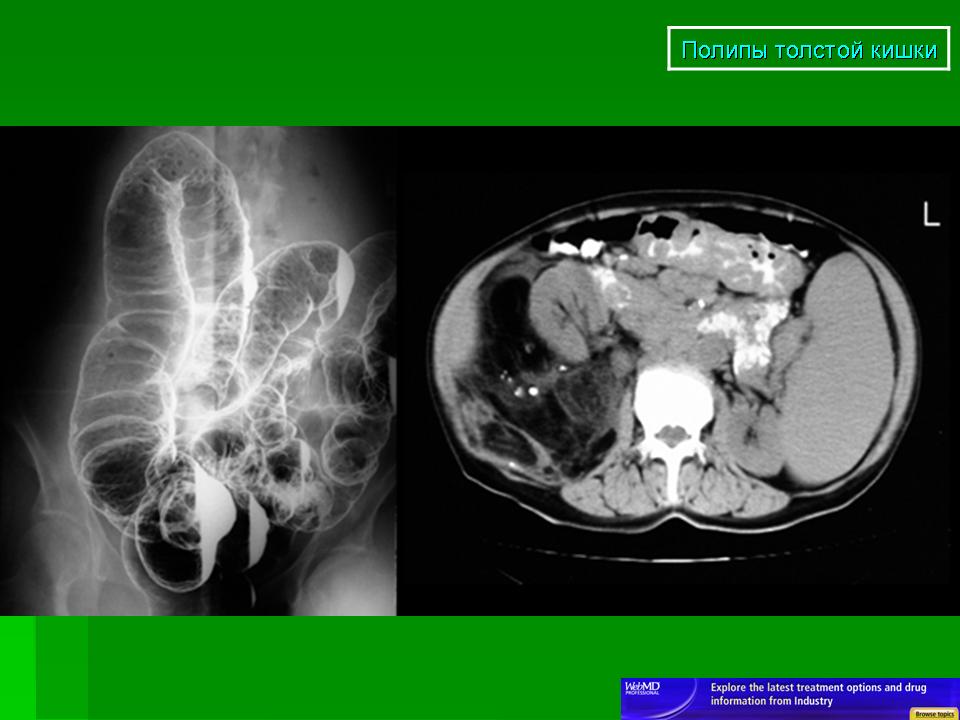

ПС. Полипы. +

Полипы